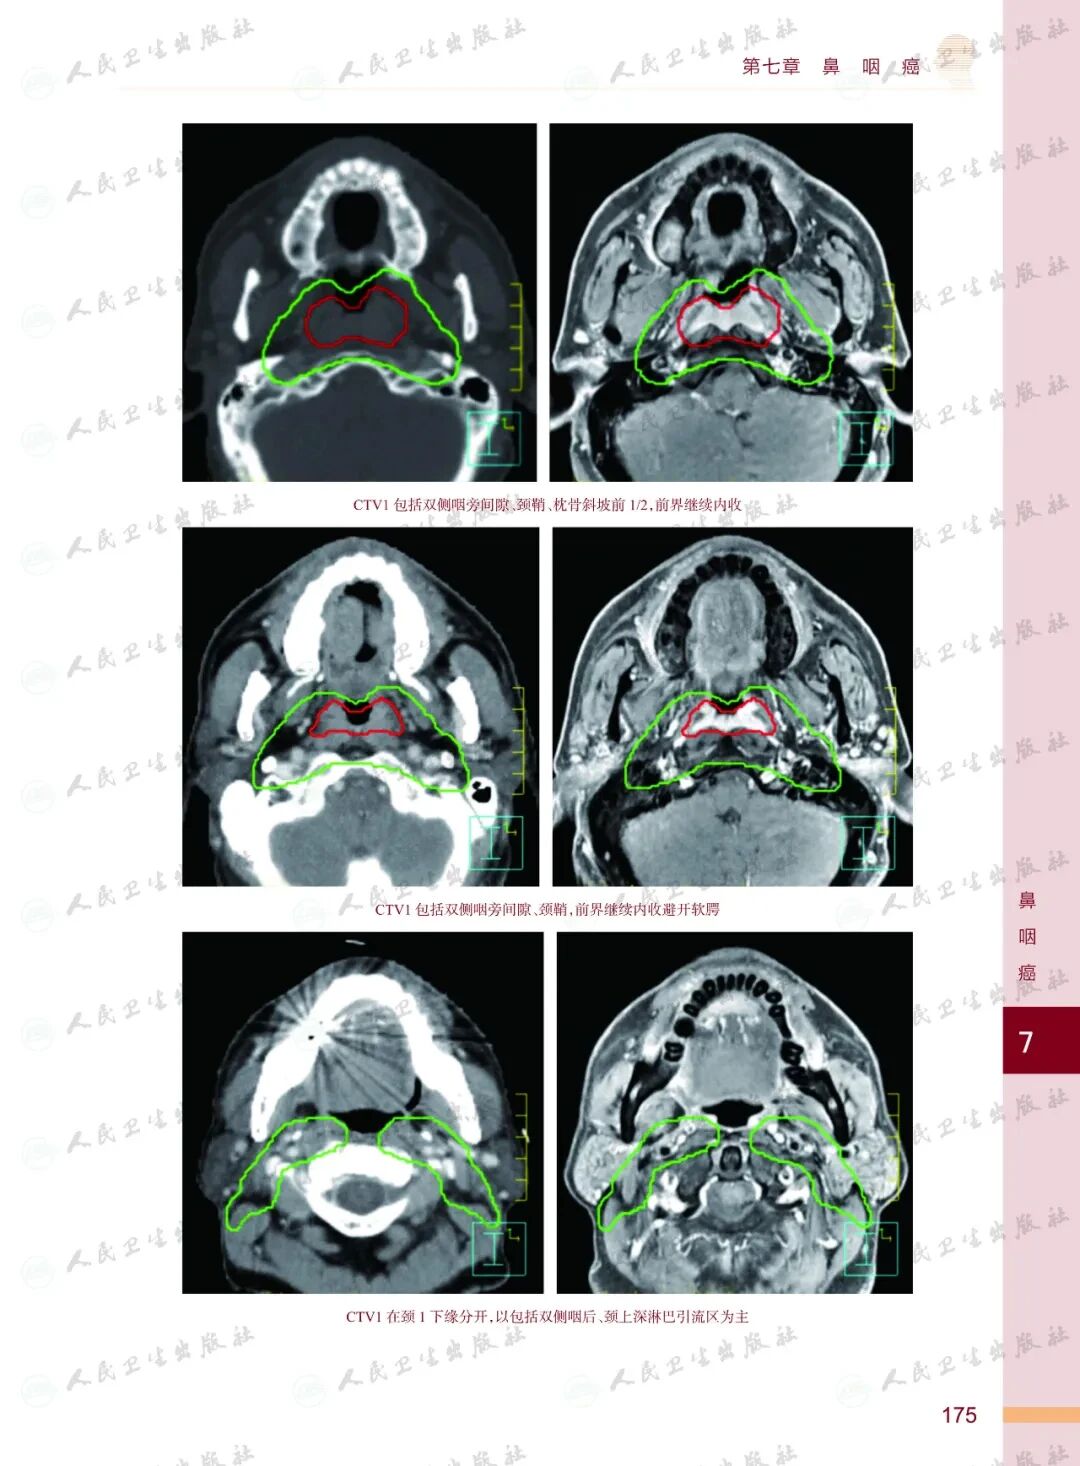

《头颈部肿瘤放射治疗图谱》

——不止是图谱,更是随唤随应的临床良师

样章试读